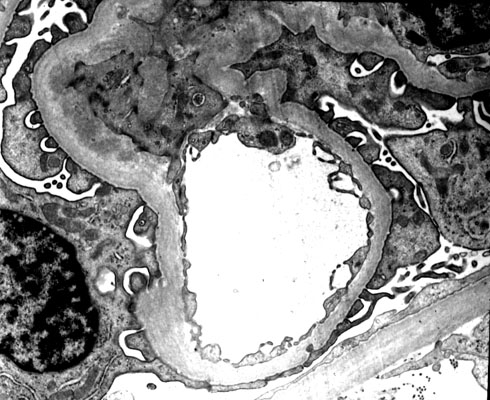

IgA nephropathy (a mesangioproliferative glomerulonephritis), EM

The glomerular mesangium is increased in thickness and cellularity